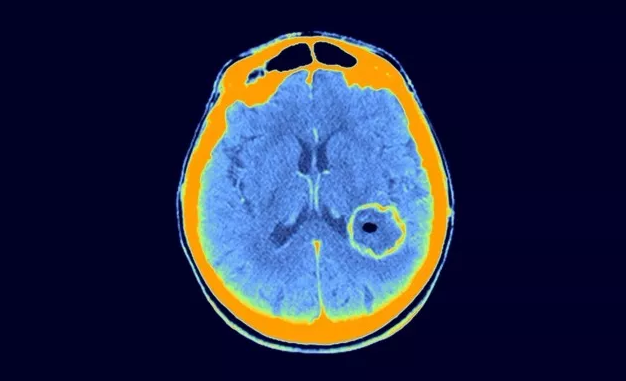

胶质母细胞瘤(患者脑扫描中所示的圆形区域)是在小鼠模型中检测的癌症之一。

分析表明,植入小鼠体内的肿瘤发生了在人体内不常见的变化。比如,人类胶质母细胞瘤倾向于获得额外的 7 号染色体拷贝。但是 Beroukhim 表示,小鼠 PDX 往往会随着时间推移而丢失这些多余拷贝。